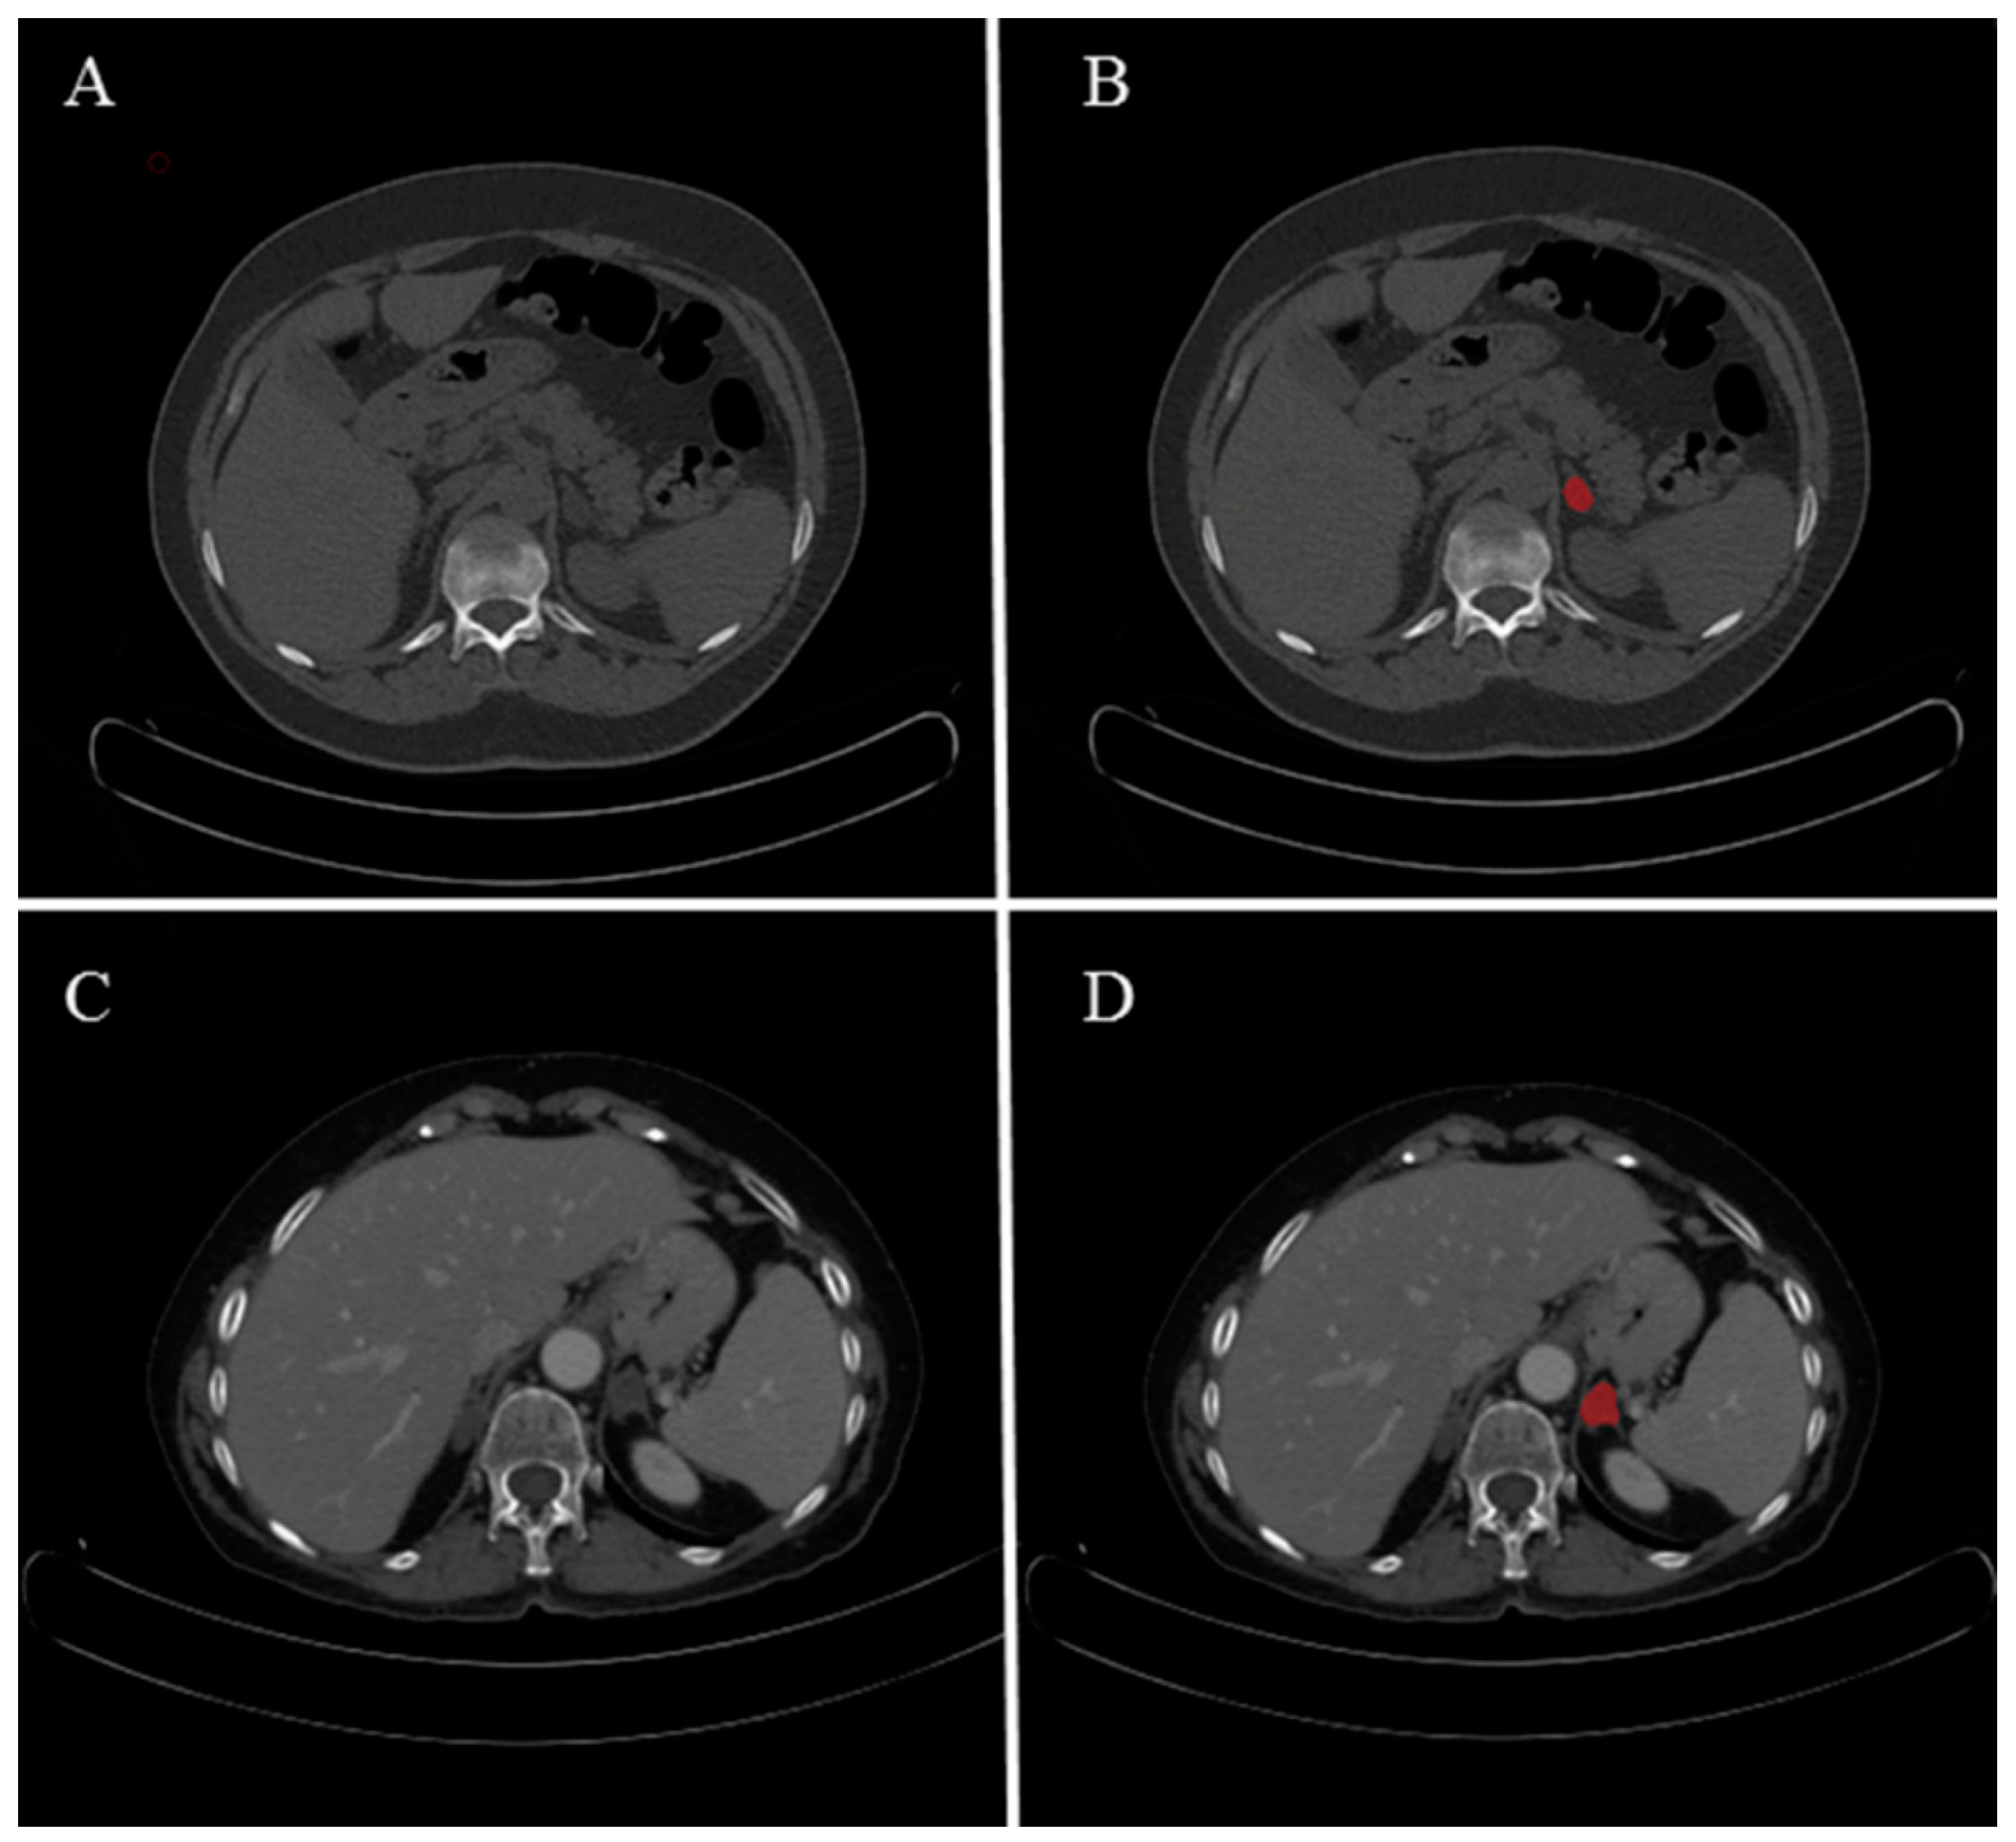

2.3. Image Segmentation